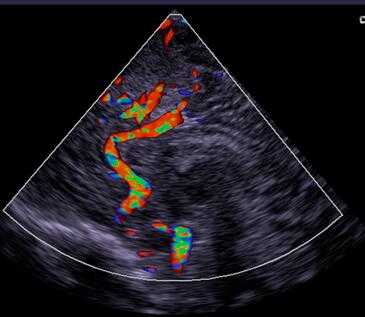

按显示方式分两大类:彩色多普勒显示;

彩超是彩色多普勒超声的简称。它是根据多普勒效应在二维超声显像(即B超)的基础上,叠加彩色血流信号,实现彩色血流显像的一种方法。